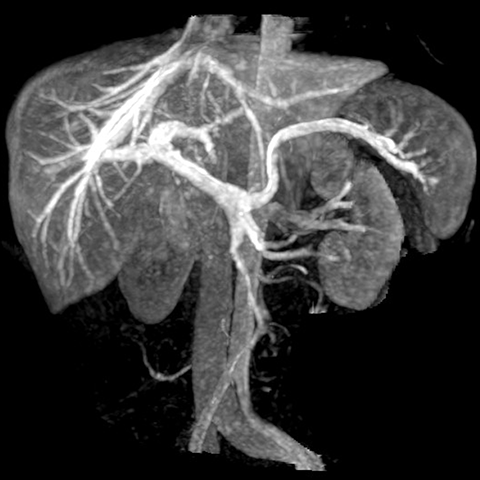

Portal and Hepatic Vein (Coronal maximum intensity projection images) [1 of 2]